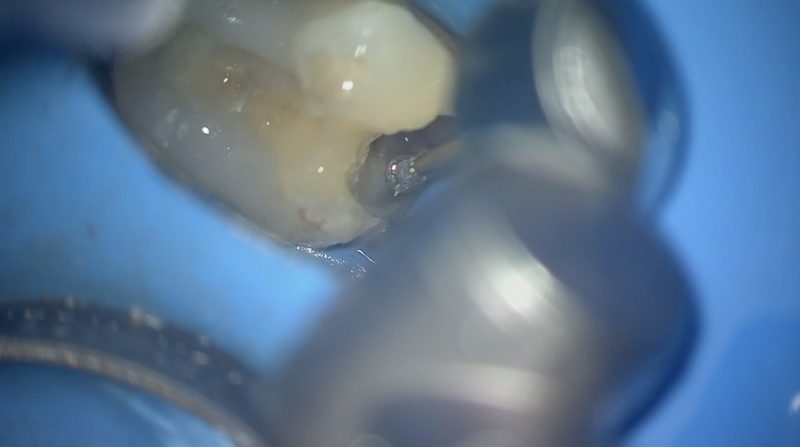

最後の隅角部の隔壁

こうしてやっと根管治療の準部が整い、その後のコアへと活用するに足る接着操作ができました。

とても地味ですが曖昧にできない大事なことだと思っています。